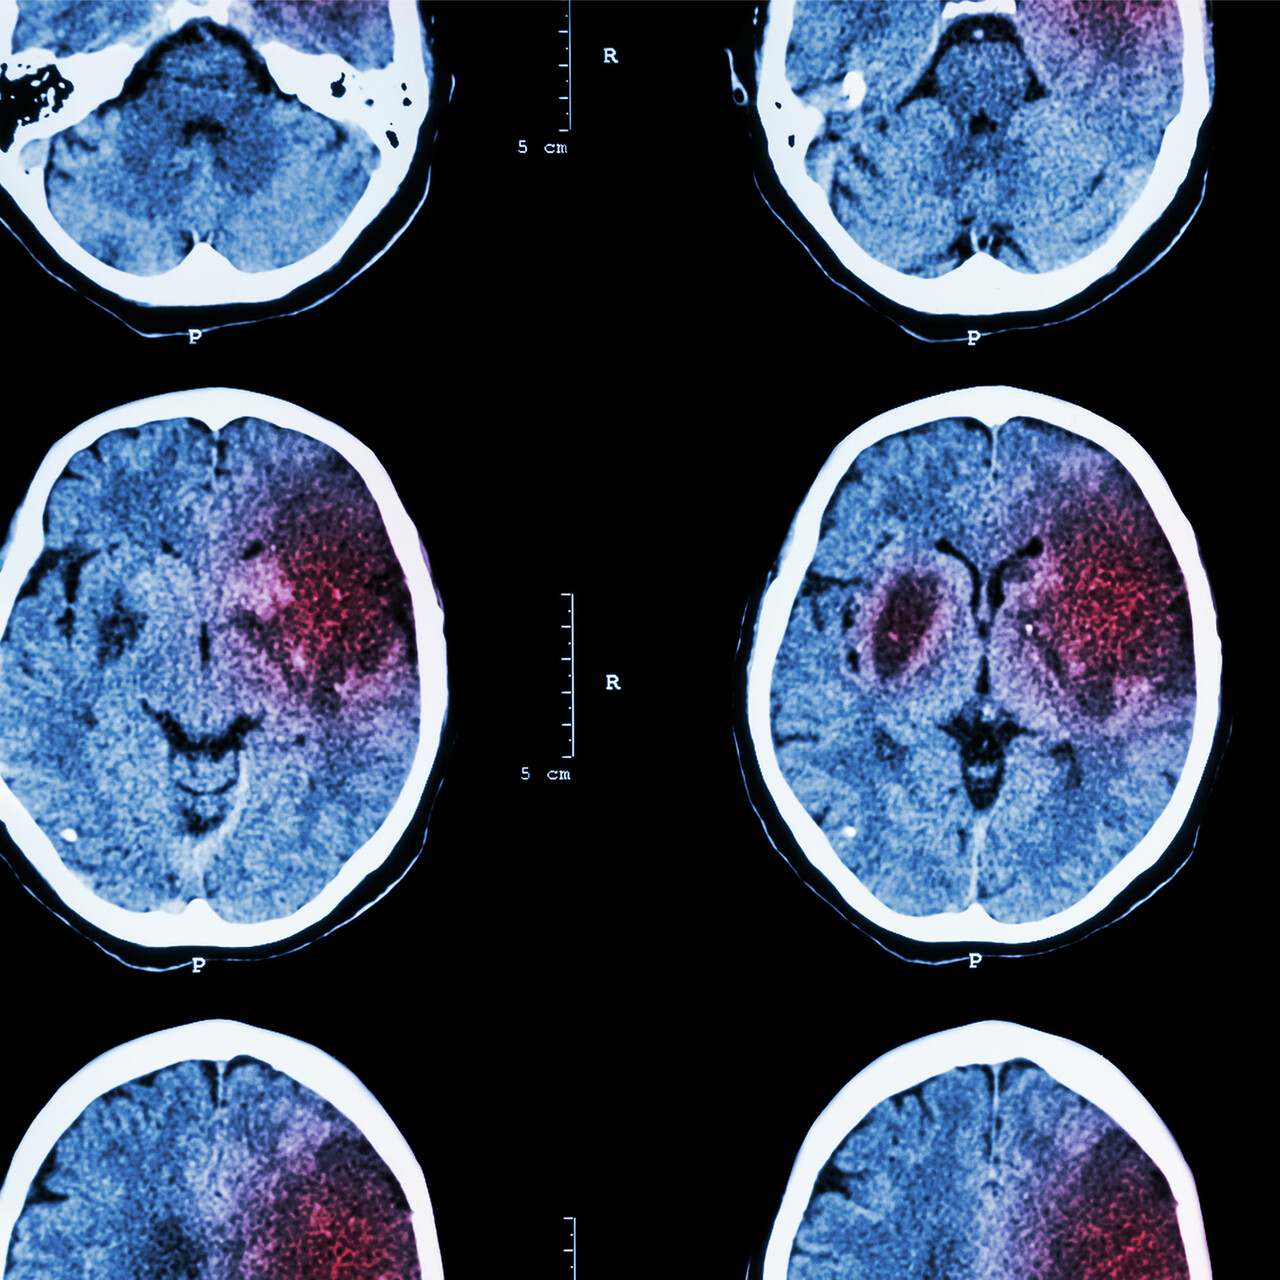

在中风发生在身体

之前我们分享令人吃惊的因素,可以设置为中风,发生在一个简短的底漆。缺血性中风,脑部血液供应受阻,防止大脑组织获得氧气。几分钟后,脑细胞开始死亡,没有直接的帮助,能够造成重大损伤甚至死亡。出血性中风,脑部动脉破裂和泄漏血液进入大脑。需要急救止血。心脏病是一个大中风的危险因素。但也有不为人知的风险考虑,其中许多影响心脏。